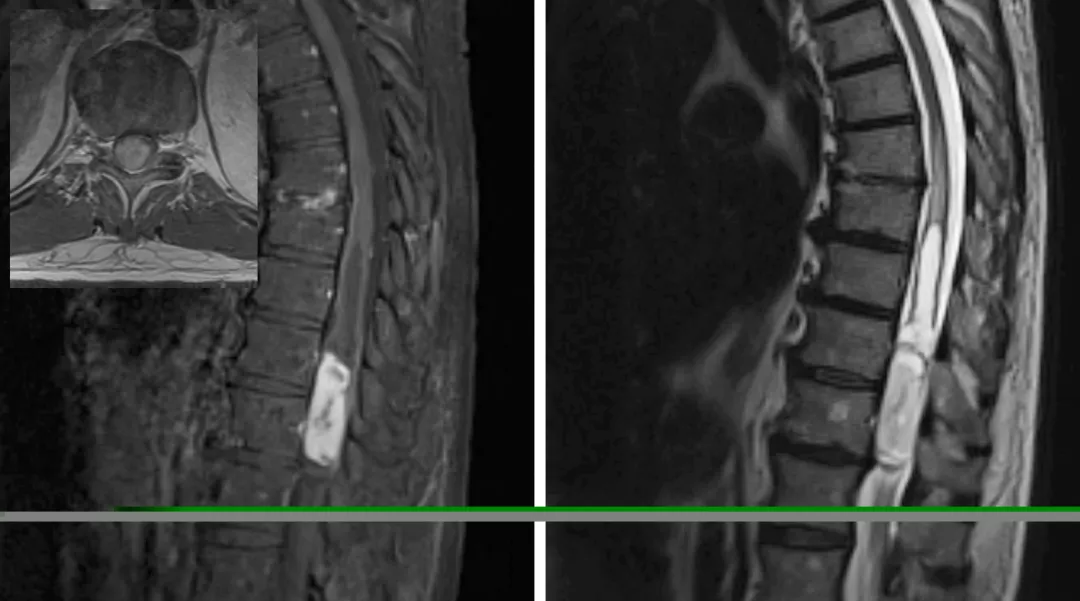

图5:图中所示为脊髓后正中沟切开脊髓切除颈髓巨大室管膜瘤的标准过程(图1显示术前图片)。仔细电凝后正中沟白质后采用蛛网膜刀切开,一把弯头吸引器或一对显微镊可用来移位或分离而不是切开后方的白质纤维(上端两幅图)。底图显示的是采用吸引器头端的特殊牵拉装置暴露肿瘤(底图)

对于体积小的髓内肿瘤可以采取整块切除,但一般体积大的肿瘤需要先进行瘤内减压或释放囊腔内容物来缩小肿瘤体积,然后再进行肿瘤切除,以免由于过度牵拉和操作损伤脊髓。

图6:采用6-0 缝线牵开软脊膜来暴露肿瘤来减少术中反复牵拉脊髓造成损伤(上图)。肿瘤上极的空洞使得瘤体与脊髓界限清晰而易于分离(中图)。底图显示采用有角度的显微剥离子将肿瘤从脊髓剥离下来(底图)。

图7:采用娴熟的显微操作技术将瘤壁自菲薄的脊髓上剥离下来。由于肿瘤出血或空洞导致脊髓与肿瘤之间形成一个明显界面。大多数室管膜瘤和脊髓之间存在明显的肿瘤-脊髓界面。一般室管膜瘤的前方均有自脊髓前动脉发出的小动脉供血。在切除肿瘤时,这些肿瘤穿支血管要仔细分离、予以电凝后切断。盲目地牵拉会导致这些血管的撕裂,从而在止血过程中可能导致临近血管和脊髓的损伤。